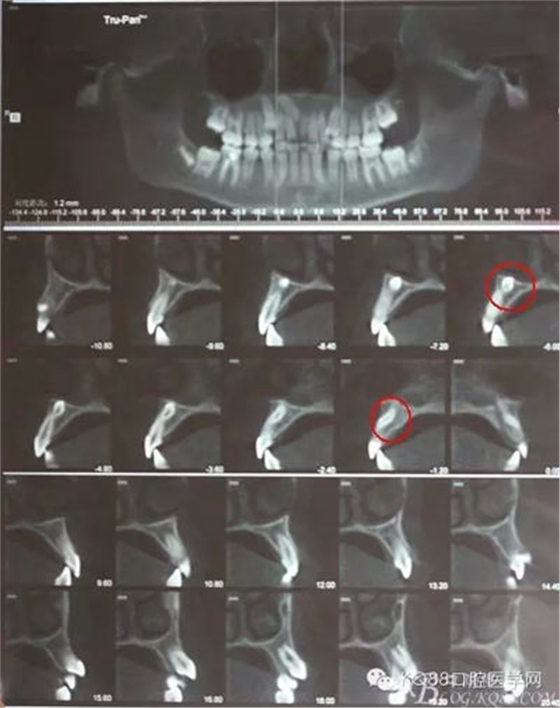

圖3.倒置多生牙位置高,又接近鼻腔,為了減小創(chuàng)傷,加拍CBCT檢查:倒置多生牙牙冠已經(jīng)突破鼻底骨質(zhì),拔除后有可能出現(xiàn)鼻腔出血,術(shù)前已經(jīng)告知患者手術(shù)風(fēng)險(xiǎn)。多生牙牙根偏向唇側(cè),為了減小創(chuàng)傷,決定從唇側(cè)做切口入路。